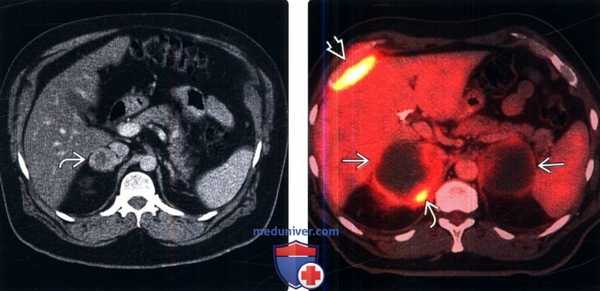

(Слева) КТ с контрастированием, аксиальная проекция: у пациента после нефрэктомии по поводу ПКР выявлено новое гиперваскуляризированное образование правого надпочечника №. В отсроченную фазу наблюдают образование без ФДГ-авидности с быстрым вымыванием контраста. Несмотря на данные результаты, наличие опухоли и анамнез пациента указывают на метастазы (подтверждено биопсией и адреналэктомией).

(Справа) ФДГ ПЭТ/КТ: у пациента, страдающего раком легких, выявлены огромные некротические метастазы в надпочечнике. Обратите внимание на скудное остаточное поглощение по периферии поражения справа и ФДГ -позитивные метастазы правой стенки грудной клетки.в) Дифференциальная диагностика при метастазах в надпочечники: